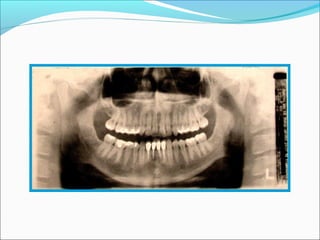

Panoramic radiography

Panoramic radiography ( rotational radiography) is a

radiographic procedure that produces a single image

of the facial structures, including both maxillary and

mandibular arches and their supporting structures

Panoramic radiography Panoramic radiography( rotational radiography) is a radiographic procedure that produces a single image of the facial structures, including both maxillary and mandibular arches and their supporting structures